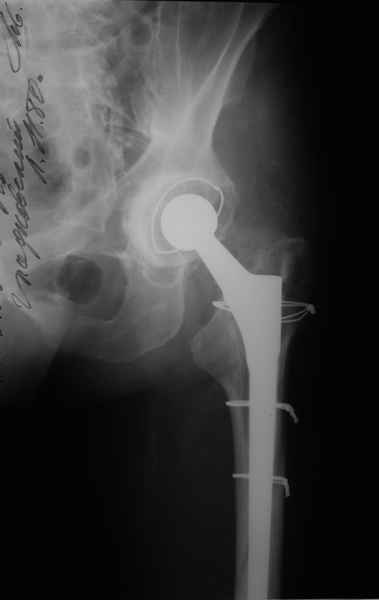

Уважаемые коллеги, продолжая дискуссию, начатую на "Вреденовских чтениях", хочу сказать, что принципиально сущестует два возможных варианта лечения.

1.Остеосинтез на ножке. Мне кажется, что применительно к этому случаю малоперспективный вариант. Синтез хорош, когда можно его выполнить в малоинвазивном исполнении и достигнуть стабильности. Действительно, если ножка б/цементной фиксации после этого не будет иметь фиксации, то ревизия не будет иметь проблем. В представленном случае стабильность синтеза сомнительная, а проведение доп.иммобилизации приведет к контрактуре суставов.

2. Применение ножки дистальной фиксации, мы отдаем предпочтение ножке Вагнера с фиксацией проксимального отдела на ножке. Более травматичное вмешательство, но при стабильной фиксации ножки реабилитация идет в обычном режиме.

Хочется показать два подобных случая, П-ка З. 72 лет и п-т Г. 80 лет. Сразу принимаю замечание, что это были ножки цементной фиксации, просто под руками не было бесцементника.

С уважением, Р.Тихилов

Произведено закрытое удлинение ножки эндопротеза с помощью ретроградного интрамедуллярного стержня. Продолжительность операции 3 часа. Два из них закрытое восстановление длины бедра диистрактором

таз-бедро.

Пациента удалось осмотреть недавно. Достигнутый результат сохраняется. Перелом бедра сросся. Конечность опорная и безболезненная, ходит без трости. Ножка, похоже, реинтегрировалась, как и надеялись. Снимки и фото в приложении. Комментарии приветствуются.

Надо ли что-то делать дальше, как полагаете? Убрать винты? Убрать "удлинитель ножки"? Или оставить все, как есть? Спасибо заранее.